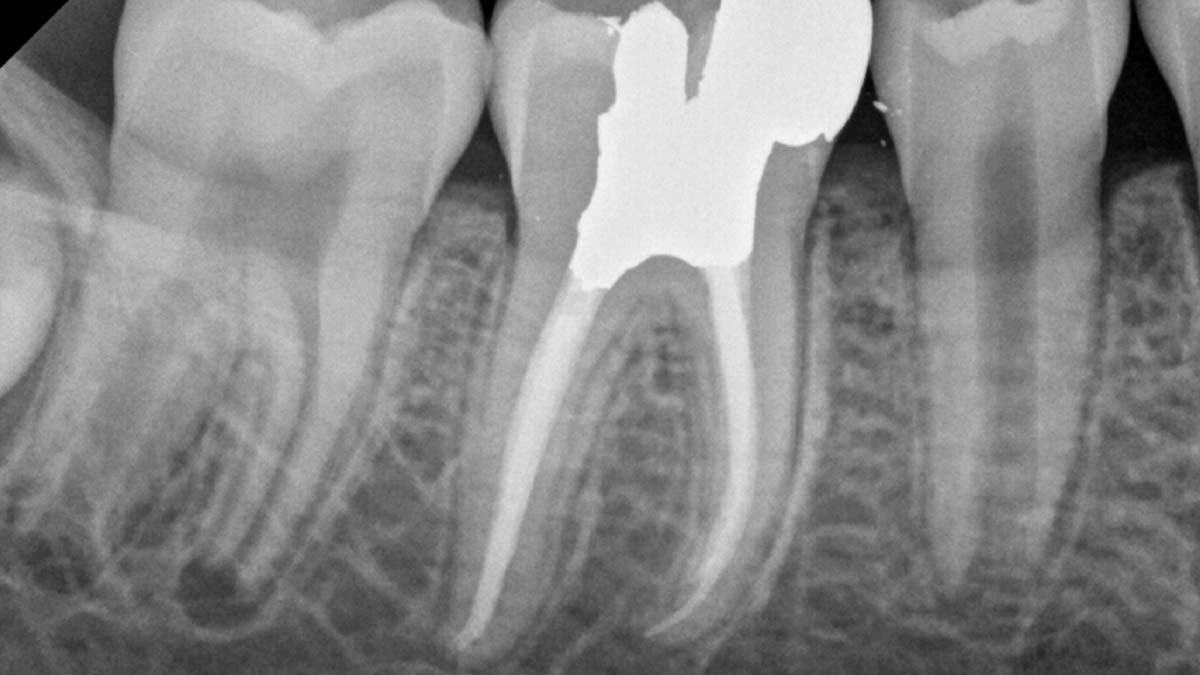

À gauche : l’utilisation de différentes formulations de gutta-percha dans un même cas peut entraîner différents degrés d’opacité.

Avec l’aimable autorisation du Dr Phillip Bell, Mooresville, NC